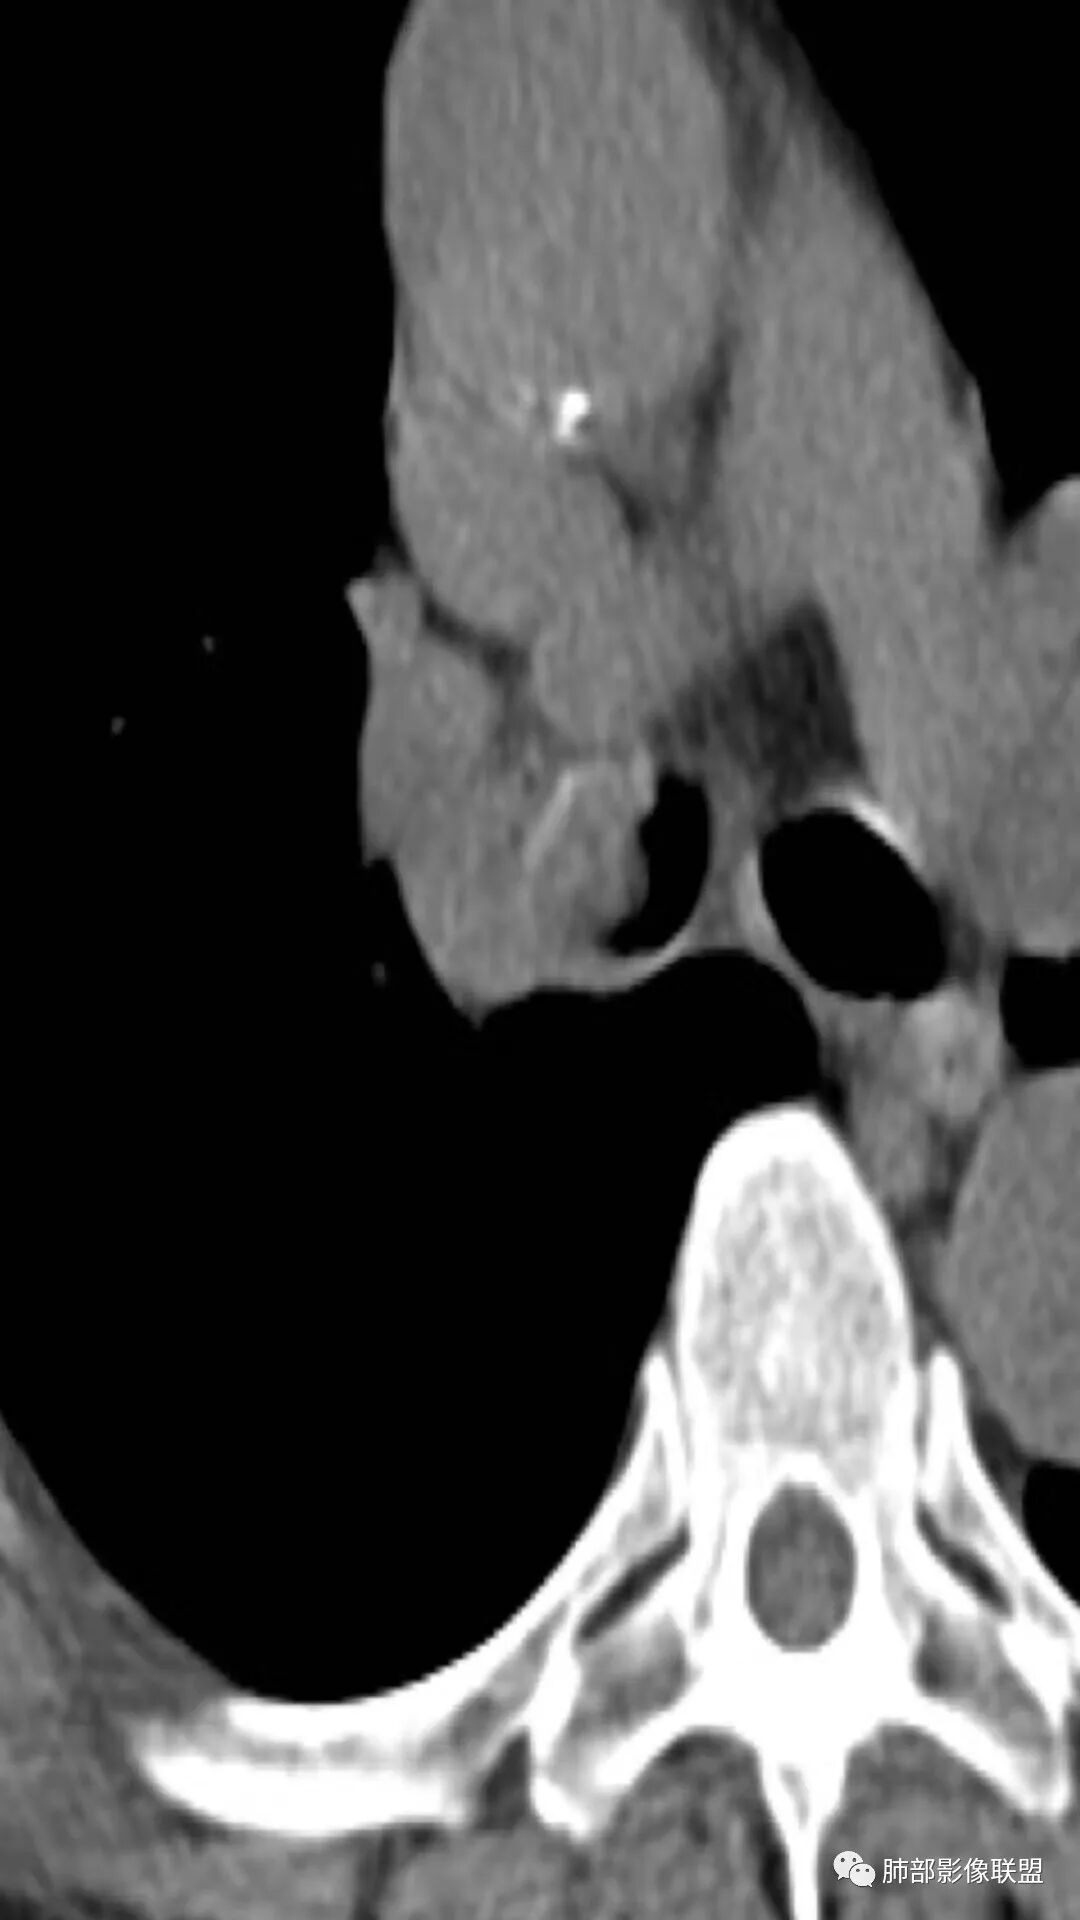

这一部分软骨还存在。

这里面是少许的泥沙样钙化吗?密度有些高

降主动脉的是噪声。病变内我总看着有小斑片的略高密度